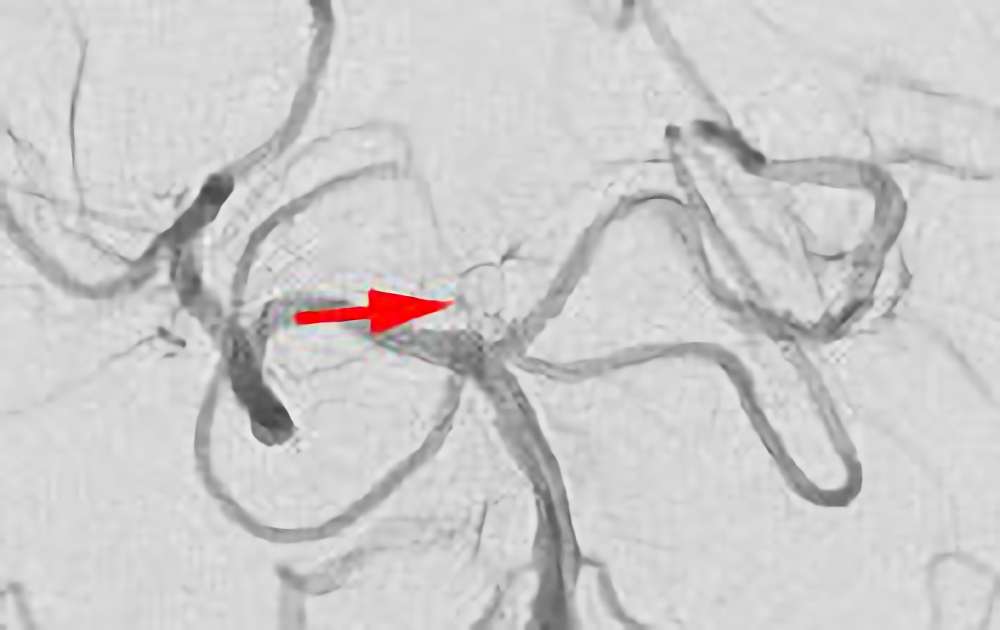

No.1631 手術後